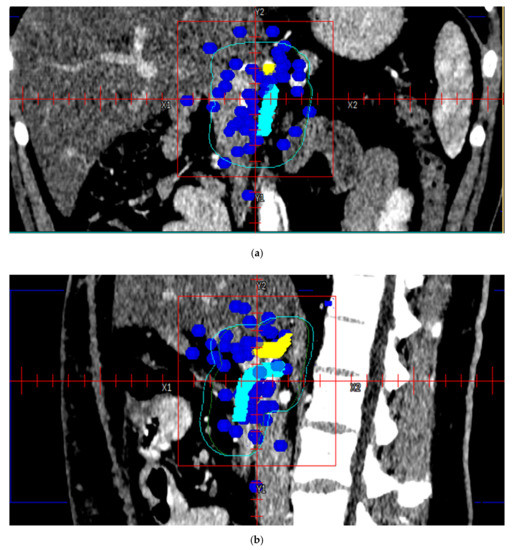

3. Results

4. Discussion